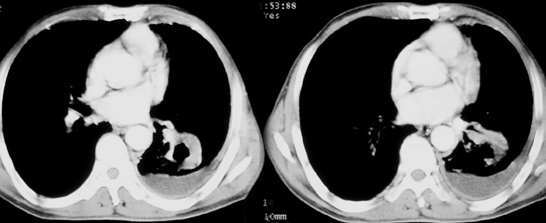

以下是引用sdqzwyx在2005-11-7 19:59:00的发言:[br]双肺弥漫大小不等的粟粒状结节影;肺纹理走行失去自然,粗细不均,边缘不规则,小叶间隔增厚;左上肺示不规则形致密影,从斑块边缘向周围伸出长短不一的致密索条影,临近的血管、支气管和叶间胸膜等结构受牵拉移位;左下肺示不规则团块状影,其内示空洞,洞内壁尚光整,左侧胸腔积液。右肺下叶背段亦示部分病灶融合。双肺可见局限性肺气肿。[br]诊断:结合病史符合三期矽肺表现(少数矽肺纤维斑块内可以形成空洞,一般认为是斑块中央感染引起坏死所致)但尘肺病人易合并肺结核,诊断可为三期+tb。所以此病人应进一步检查是否合并结核。